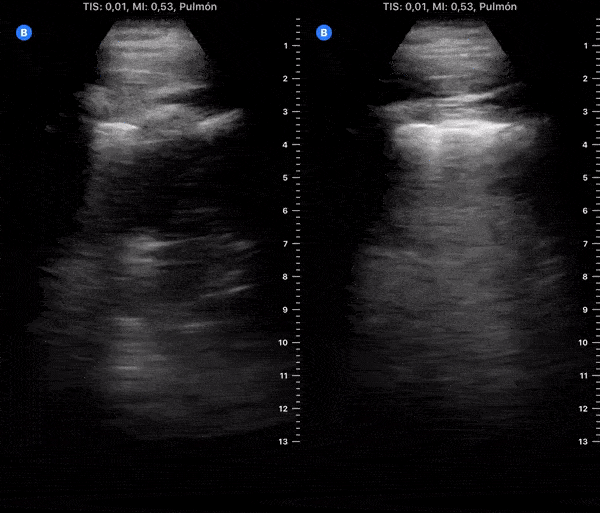

COVID 19 Lung US Disease Progression - Day 18

Day 18 after #COVID diagnosis. Similar cough. No fever or dyspnea. SpO2 97%. #POCUS update: slight worsening. Bilateral thickened pleura & B-lines, subpleural consolidation reappeared. On HCQ (D14). Waiting to re-test on friday. @yaletung